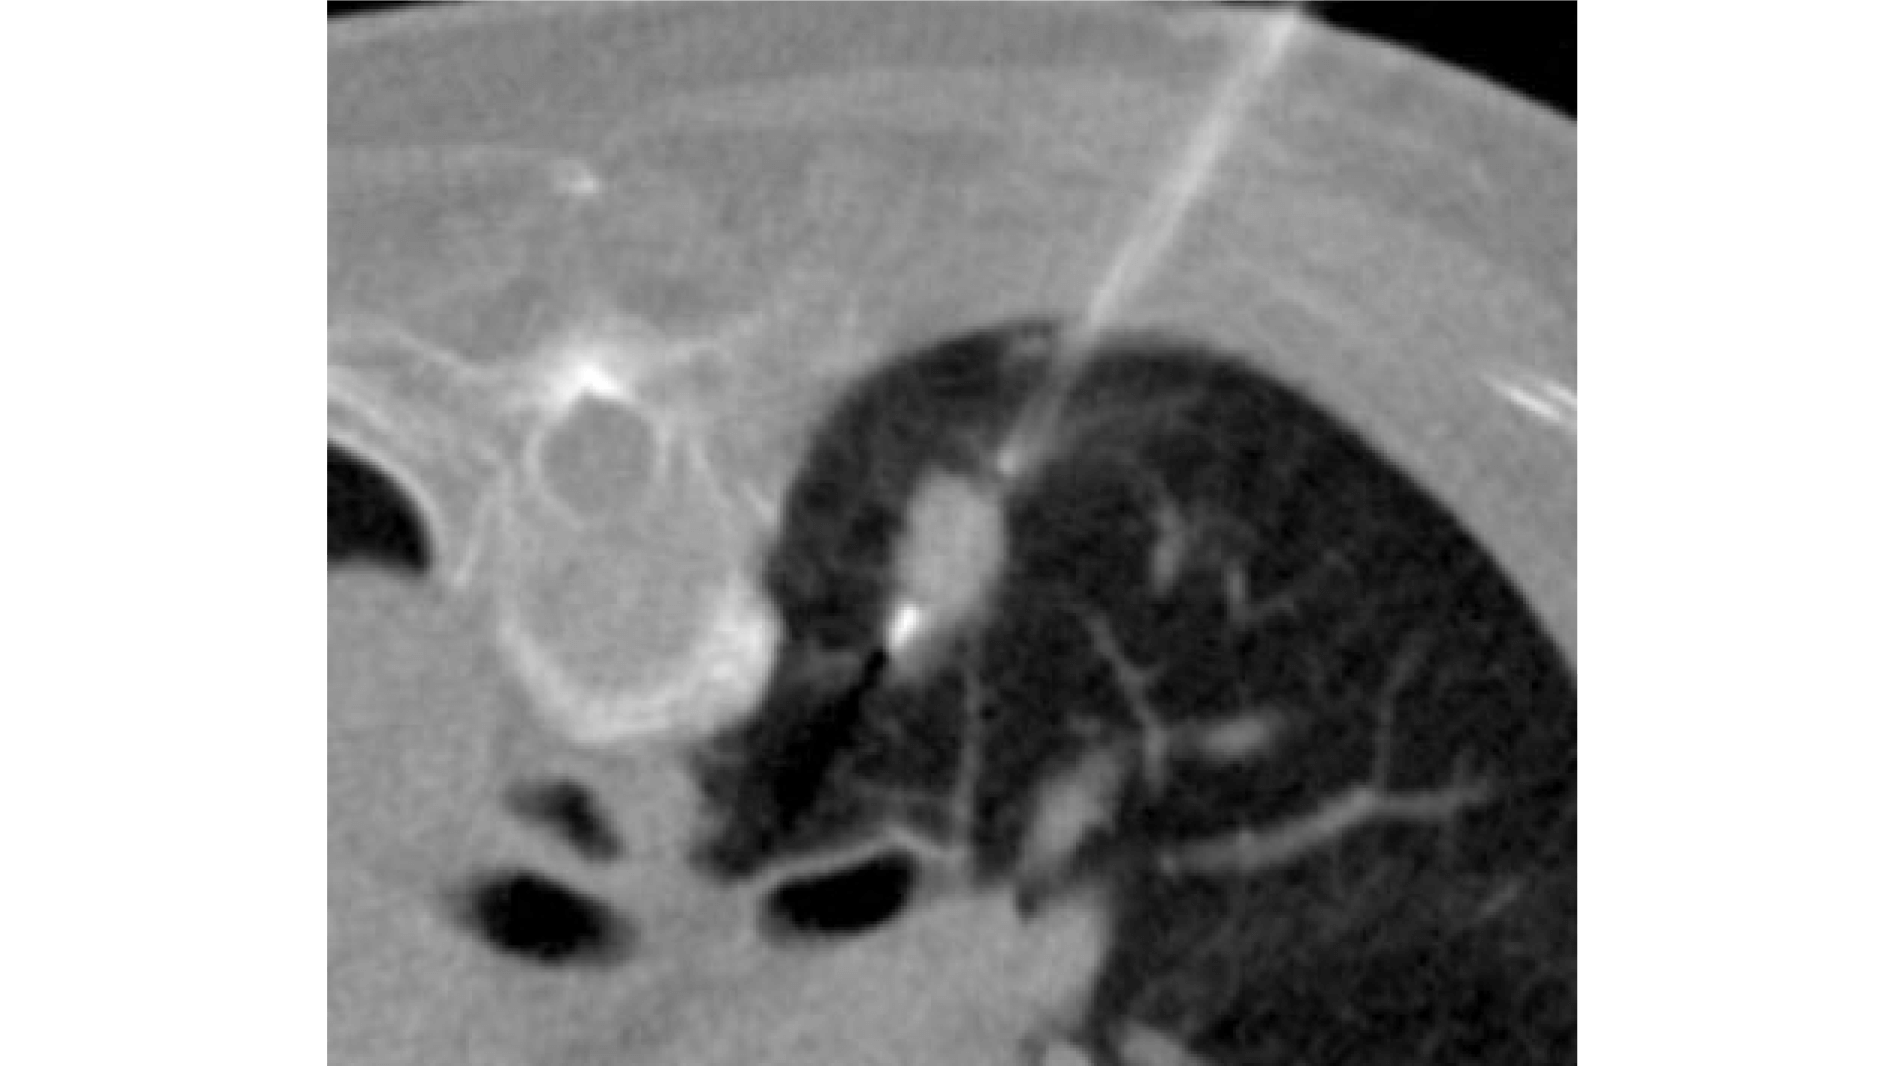

病変の場所によっては、気管支鏡では組織を採取しにくい場合もあります。特に肺の端のほうに病変がある場合は、CTガイド下生検を行います。この検査は、CT画像で病変の位置を確認しながら、体の外から針を刺して組織を採取する方法です。

CTガイド下生検は放射線科で行われることが多いですが、当院では呼吸器内科の医師がこの検査を行っています。これにより、待ち時間の短縮、迅速な診断が可能になります。さらに、複数の病変がある場合でも、病気を熟知している呼吸器の医師が、診断に適した部位を選択して組織を採取することができます。

気管支鏡検査とCTガイド下生検の両方を行える体制を整えることで、それぞれの検査の長所を生かし、補い合い、より質の高い医療の提供につなげています。

CTガイド下生検のようす